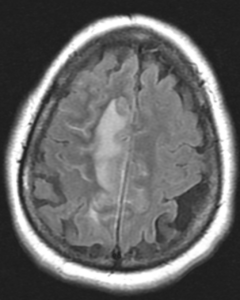

Figure 1A: T2/FLAIR sequence demonstrating right greater than left parasagittal frontal and parietal cortical T2/FLAIR hyperintensity and edema with involvement of the subcortical and deep white matter. There is also incomplete FLAIR suppression of the cerebrospinal fluid in the adjacent sulci, indicative of an inflammatory process. (Click to enlarge.)

Magnetic resonance imaging (MRI) of her brain revealed a right parasagittal T2/FLAIR, and cortical and subcortical white matter hyperintensity with gyral enhancement concerning for primary or metastatic malignant disease.